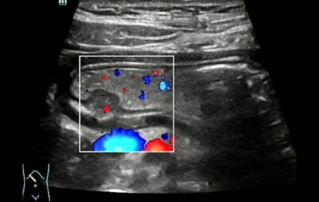

Endocavity ?? ?? ?? ???(DE10-3WU, Resona 7, Mindray)? ??? ??? ???? ?? ?? ????(Levator ani nuscle)? ??? ???. ???? ?? ??? 3~4mm? ????, ???(levator hiatus) ?? ?? - 6.13cm, LUG1(??? m ??? ??. Bulbocavernosus) ŌĆō 2.95cm ? LUG2 ŌĆō 3.15cm(?? 2.5cm ??)

??????? ??? ?? ? ??? ??? ??? ?????, ?? ??(pelvic floor) ??? ??? ?? ??(??? ?/?? ??)? ??? ???. ? ?? ???? PVA, RVA ? PUA ?? 20┬░ ???? ?????. ? ?? ???? PVA ŌĆō 134o, RVA ŌĆō 82o ? PUA ŌĆō 119o.

??? ???? ??? ?? ????? ??? ??? ?? ?????. ????? ? ??? 30mm?? 42mm?? ??? ? ??? ??? ??? ????? ?? ? ? ?? ? ?? ? ?? ??? ??? ??? ? ????. ?? R ? ???? ?? ?? ?? ?? ?? 7mm, ?? ?? 8mm???.